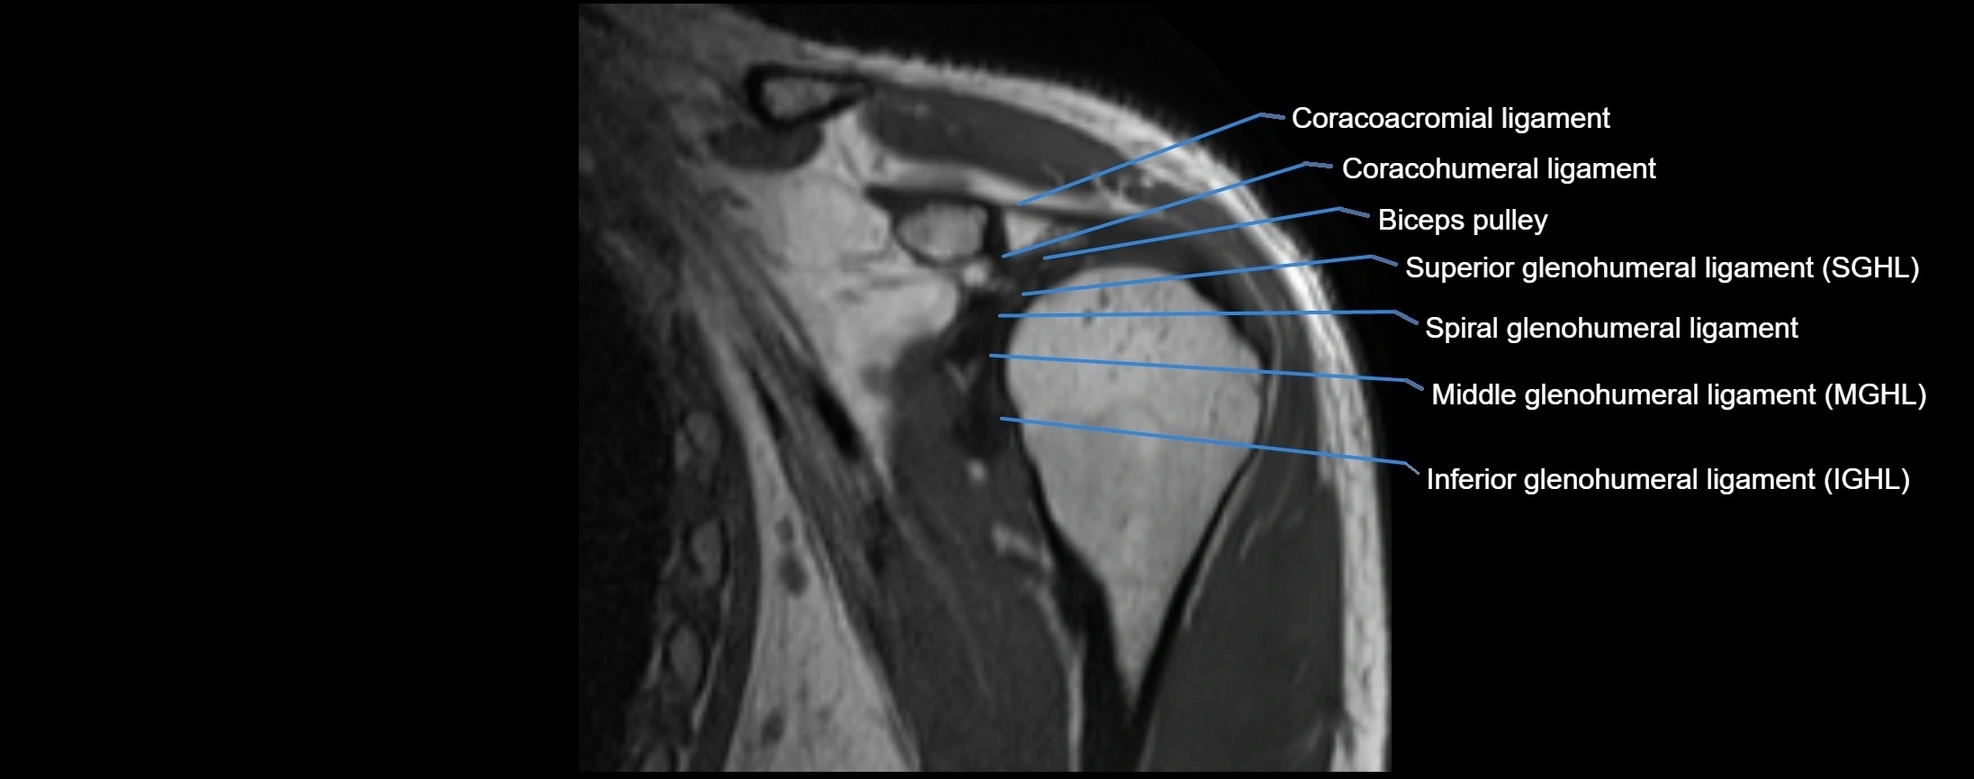

CT image

image